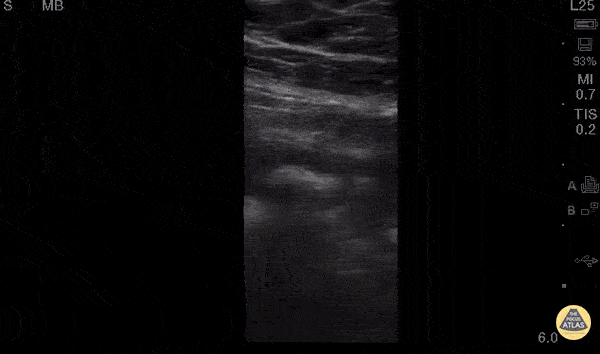

Bowel-GI - Appendicitis Longitudinal

30 y/o M w/ subjective fever, RLQ pain x1day. Tenderness in McBurney’s point w/positive Rovsing’s and Psoas signs, labs significant for mild leukocytosis. POCUS w/ linear probe placed on area of maximal tenderness in RLQ. Transverse and longitudinal views demonstrated non-compressible, blind-ended, non-peristalsing, tubular structure with surrounding hypoechoic free fluid. A central hyperechoic structure representing a fecalith can be appreciated. Outer diameter was measured to be 10mm representing dilated appendix. Findings of acute appendicitis were confirmed with official ultrasound and pt was taken to OR for appendectomy without CT (limiting radiation for young adult). While POCUS is operator dependent and CT is gold-standard for diagnosis of appendicitis in adults, our POCUS findings had higher positive-predictive value given high pre-test probability (classic sx of appendicitis, alternate diagnoses less likely) and optimal pt for study (thin male, no prior surgeries). Dr. Robert Allen and Dr. Matthew Riscinti - Kings County Emergency Medicine